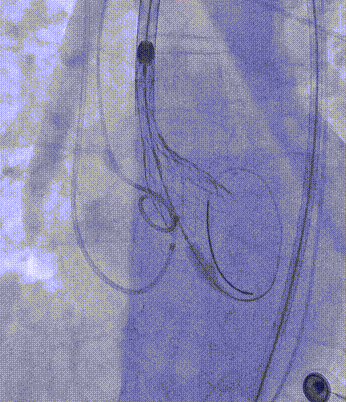

构建轨道,加硬导丝送入左室,起搏180bpm,22x40mm球囊预扩,快速抽瘪球囊后撤出。

置于TAV27瓣膜输送系统,主动脉根部造影,定位输送系统位置。

瓣膜释放1/3时,起搏160bpm,快速释放至3/4处,瓣膜正常工作后,观察冠脉风险,反流情况。超声医师的协助下,使用食道超声实时评估瓣膜形态、植入深度、返流及瓣周漏,讨论后决定24x40mm球囊后扩。

食道超声再次评估瓣膜形态,位置可,瓣叶启闭正常,未见瓣周漏及反流。

撤出器械,闭合入路。术后超声再次评估瓣膜形态,位置可,开发可,未见瓣周漏及反流,手术圆满完成。